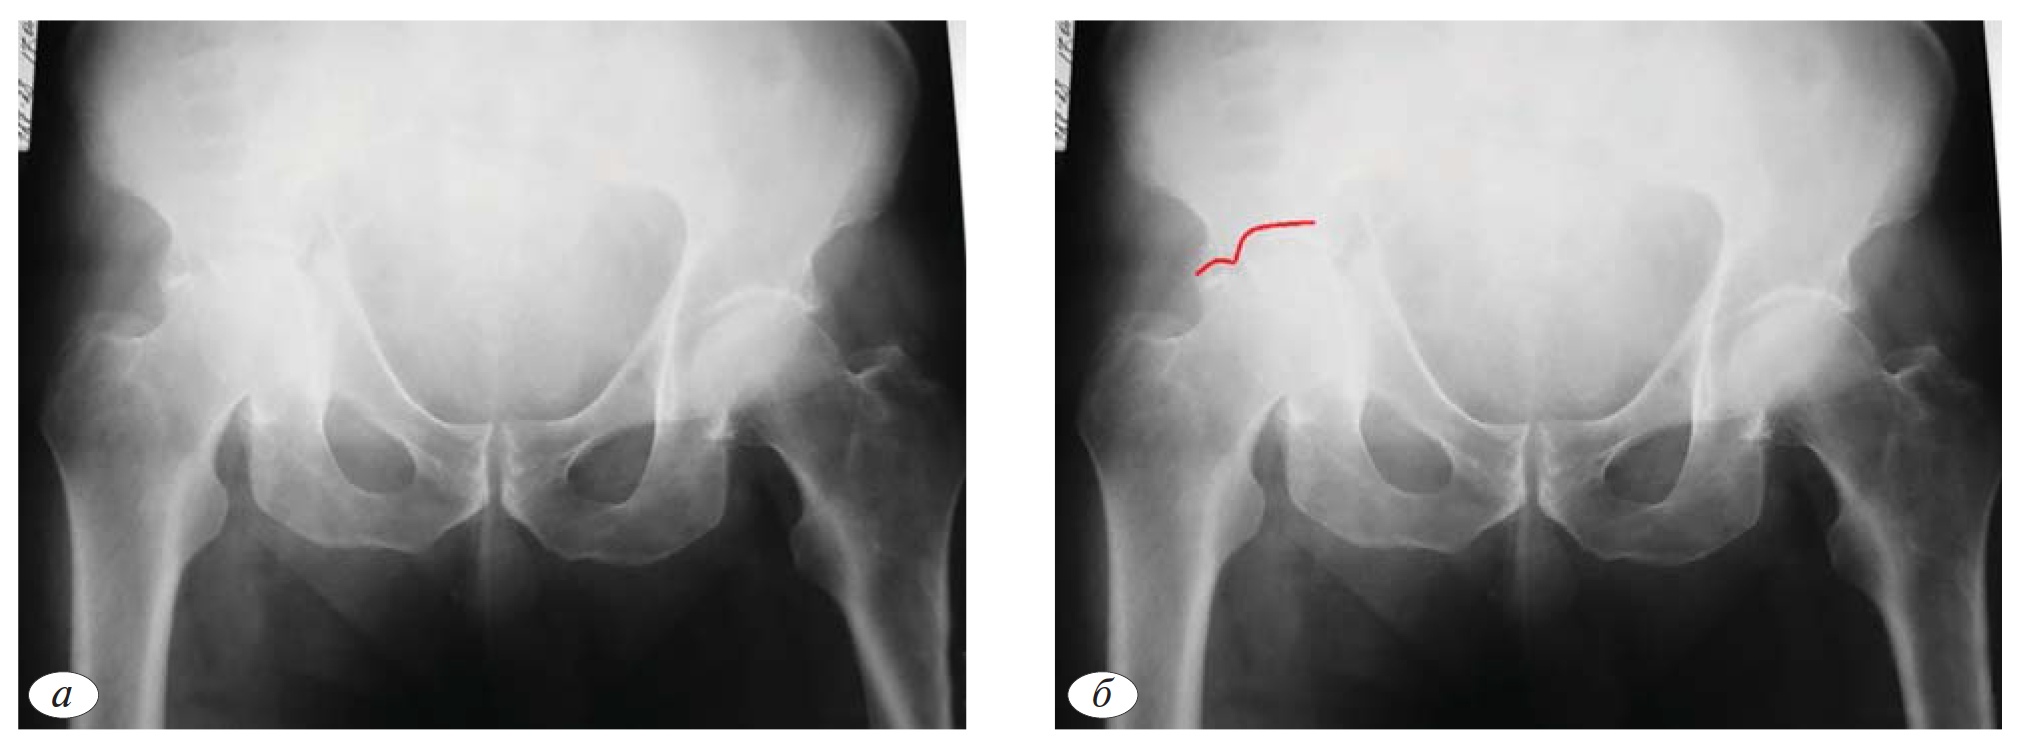

На обзорной рентгенограмме таза (рис. 1, а) определяется сочетание нарушений контуров трех линий (подвздошно-гребешковая, подвздошно-седалищная, контуры запирательного отверстия), характерное только для 3 типов ассоциированных переломов: Т-образного перелома, перелома передней колонны, ассоциированного с задним полупоперечным переломом, двухколонного перелома. Таким образом, на первом этапе из 10 возможных типов переломов, мы можем исключить 7 типов (рис. 1, а).

Целостность крыла подвздошной кости, как уже было отмечено ранее, позволяет исключить типы переломов, при которых наблюдается отдельный фрагмент передней колонны (перелом передней колонны, ассоциированный с задним полупоперечным переломом, двухколонный перелом). Таким образом, методом исключения диагностирован Т-образный перелом (рис. 1, в).

Рис. 1.а — обзорная рентгенография таза при поступлении; б — первый этап определения атипичного Т-образного перелома ассоциированного с переломом задней стенки; в — второй этап определения атипичного Т-образного перелома ассоциированного с переломом задней стенки; в — окончательное определение атипичного Т-образного перелома ассоциированного с переломом задней стенки; г, д, е, ж, з — детализация атипичного Т-образного перелома ассоциированного с переломом задней стенки с помощью прицельных рентгенограмм в подвздошной и запирательной проекциях и компьютерной томографии.

Однако при дальнейшем анализе обзорной рентгенограммы обращает на себя внимание отдельный фрагмент задней стенки. Соответственно в данном клиническом примере имеет место не Т-образный перелом, а атипичный Т-образный перелом, ассоциированный с переломом задней стенки (рис. 1, в).

Выполнение прицельных рентгенограмм и КТ позволяет подтвердить характер перелома. Как на рентгенограммах, так и на КТ отчетливо видна поперечно ориентированная линия перелома, проходящая через свод вертлужной впадины (транстектальный перелом), которая разделяет латеральные отделы тазового кольца на крыло и тело подвздошной кости и лобково-седалищный сегмент.

На прицельной рентгенограмме в запирательной проекции и КТ определяем отдельную плоскость излома, которая располагается в области задней стенки (рис. 1, д, з).

На рис. 1, ж видна вертикальная линия перелома, которая разделяет лобково-седалищный сегмент на передний и задний фрагмент (линия проходит через четырехстороннюю пластинку). Очень важно при планировании операции учитывать, что лобково-седалищный сегмент состоит из двух фрагментов.